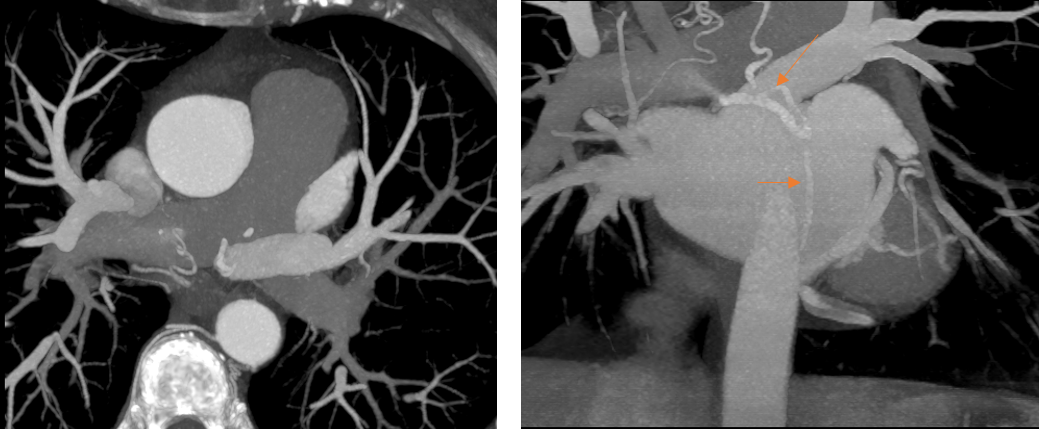

Figura 3: Fig 3 reconstrucţii oblic coronale MIP (maxim intensity projection) din achiziţie angioCT coronariană

Fig 4 reconstrucţii volumice (VRT) din achiziţie angioCT coronariană

Discuţie caz nr 50: Examinarea angioCT coronariană este actual indicație de clasa 1 la pacienții cu boală coronariană cronică; este cazul unui pacient care a fost diagnosticat la examinare angioCT cu fistulă între arteră coronară dreaptă și arteră pulmonară dreaptă.